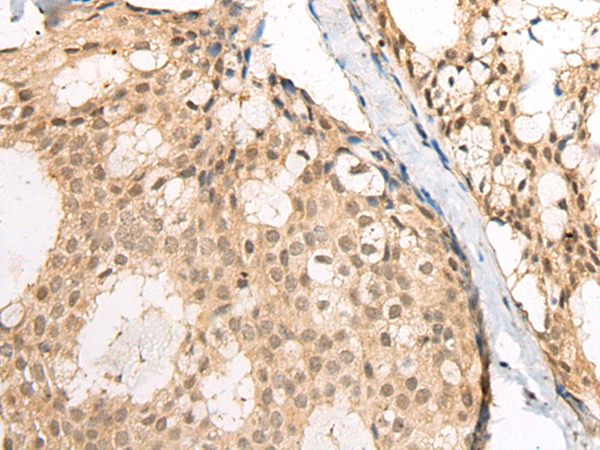

IHC positive control:

Human liver cancer and human breast cancer

IHC Recommend dilution:

25-100